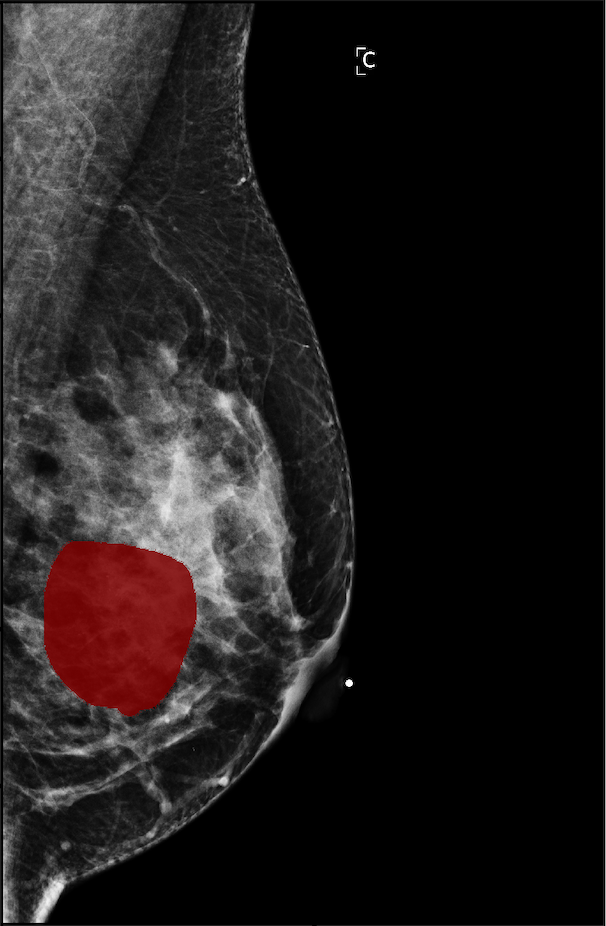

The NYU Breast Cancer Screening Dataset [78] includes 229,426 exams (1,001,093 images) from 141,472 patients.222Our retrospective study was approved by our institutional review board and was compliant with the Health Insurance Portability and Accountability Act. Informed consent was waived. Each exam contains at least four images which correspond to the four standard views used in screening mammography: R-CC (right craniocaudal), L-CC (left craniocaudal), R-MLO (right mediolateral oblique) and L-MLO (left mediolateral oblique). An example is shown in Figure 3.

For all exams matched with biopsies, we asked a group of radiologists (provided with the corresponding pathology reports) to retrospectively indicate the location of the biopsied lesions. This way we obtained the segmentation labels: where if pixel belongs to the benign/malignant findings. An example of such a segmentation is shown in Figure 3. In all experiments (except for experiments in Section 3.6 that assess the benefits of utilizing segmentation labels), segmentation labels are only used for evaluation. We found that, according to the radiologists, approximately of exams were mammographically occult, i.e., the lesions that were biopsied were not visible on mammography, even retrospectively, and were identified using other imaging modalities: ultrasound or MRI.

In Figure 7, we visualize saliency maps for four samples selected from the test set. In the first two examples, the saliency maps are highly activated on the annotated lesions, suggesting that our model is able to detect suspicious lesions without pixel-level supervision. Moreover, the attention is highly concentrated on ROI patches that overlap with the annotated lesions. In the third example, the saliency map for benign findings identifies three abnormalities. Although only the top abnormality was escalated for biopsy and hence annotated by radiologists, the radiologist’s report confirms that the two non-biopsied findings have a high probability of benignity and a low probability of malignancy. In the fourth example, we illustrate a case when there is some level of disagreement between our model and the annotation in the dataset. The malignancy saliency map only highlights part of a large malignant lesion with segmental coarse heterogeneous calcifications. This behavior is related to the design of : a fixed pooling threshold cannot be optimal for all sizes of ROI. The impact of is further studied in 3.6. This example also illustrates that while human experts are asked to annotate the entire lesion, CNNs tend to emphasize only the most informative regions. While no benign lesion is present, the benign saliency map still highlights regions similar to that in the malignancy saliency map, but with a lower probability than the malignancy saliency map. In fact, calcifications with this morphology and distribution can also result from benign pathophysiology [42].